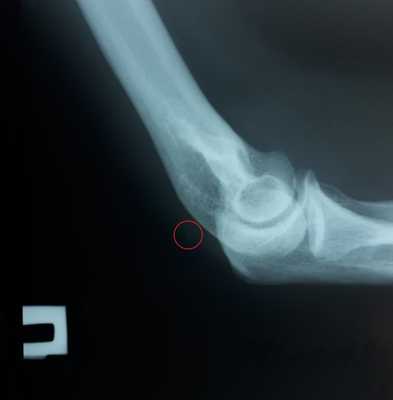

При выполнении рентгенограмм иногда можно увидеть отрыв небольшого костного фрагмента от локтевого отростка.

Рассчитывать на этот признак при диагностике не стоит. Но его наличие следует трактовать как отрыв трицепса и делать МРТ для его исключения.

Исследования изображений помогают определить уровень поражения (прикрепление к локтевому отростку, миотендинозное соединение или внутримышечное), отличить частичный разрыв от полного, оценить величину ретракции сухожилия, а также исключить любые связанные с этим повреждения костей. Боковые рентгеновские снимки локтя полезны для подтверждения диагноза при наличии небольшого внесуставного отрывного перелома локтевого отростка (признак чешуйки) Рентгеновские снимки (передне-задний и боковой) и компьютерная томография (КТ) также полезны для диагностики травм, связанных с разрывом трехглавой мышцы, таких как ипсилатеральная перелом головки лучевой кости и перелом головки локтевой кости. Можно использовать ультразвуковое исследование, но оно дает ограниченные анатомические детали. МРТ является лучшей методикой для оценки повреждений сухожилий, поскольку она предоставляет более подробную информацию о повреждении: степени поражения и ретракции сухожилия [9][10]. Тендинит трицепса является нехарактерным.